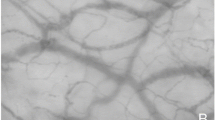

With OCTA it was possible to obtain detailed images of the sublingual microcirculation. In longitudinal sections of the sublingual mucosa (Fig. 1A), the stratified squamous epithelium could be distinguished from the lamina propria. The median thickness of the stratified squamous epithelium was 120 μm [104; 149]. In these images, vessels could be identified by color coding as red dots (cross-cut) or as red lines (cut longitudinally). The vascular leading layer, which could be detected by OCTA had a median thickness of 409 μm [361; 451]. Most vessels were detected in the lamina propria and interdigitated with the rete ridges of the overlying epithelium. Single capillaries followed the connective tissue papillae of the lamina propria and reached up to half the thickness of the stratified squamous epithelium. Individual capillaries as well as larger, deeper vessels could be recognized in transversal images (en face images, Fig. 1,B–D) of the sublingual microcirculation. In addition, characteristic vessel formations of the oral microcirculation could be identified by OCTA (Fig. 2).

Optical coherence tomography angiograms of the sublingual microcirculation. Optical coherence tomography (OCT) angiograms of the sublingual microcirculation. Cross-sectional image (B-scan; (A) with perfused vessels visible as red dots. The white double arrow shows the stratified squamous epithelium. En face OCT angiograms (B,C) and color-coded OCT angiogram (D) of the same area of the sublingual mucosa. Circle 2 (C) indicates the region which was used for calculation of the flow density (central ring). The flow density (whole en face) is the average flow density of circles 1 and 2. A: 1 × 1 mm; B – D: 3 × 3 mm scans.

Comparison of characteristic vessel configurations of the oral mucosa imaged by optical coherence tomography angiography and incident dark field illumination. Vessels of the tongue papillae recorded by optical coherence tomography angiography (OCTA; (A), 0.75 × 0.75 mm) and incident dark field illumination (IDF; (B), 1.1 × 1.1 mm). Vascular loops of the sublingual microcirculation recorded by OCTA (C), 1.1 × 1.1 mm) and IDF (D), 1.1 × 1.1 mm).

Compared to OCTA images, those produced by IDF were sharper so that individual vessels were more easily distinguishable (Fig. 2, B,D). In contrast, capillaries located deeper in the tissue were revealed with OCTA, which did not show up on IDF illumination imaging (for example, vascular connections between vessel loops; Fig. 2,C).

Analysis of the perfused vessel density in optical coherence tomography angiograms of the sublingual microcirculation. En face optical coherence tomography (OCT) angiogram (A) of the sublingual microcirculation. For analysis of the perfused vessel density (PVDby OCTA), a picture section (box with dashed line; 858 × 688 µm) was exported from the OCT angiogram, within which the vessel length relative to the image size was determined. Picture (B) shows a picture of the sublingual microcirculation recorded by incident dark field illumination (688 × 688 µm).

Video microscopy using SDF and IDF is the current gold standard for evaluating the sublingual microcirculation26. In this study, videos of the microcirculation were recorded using IDF illumination imaging, which allowed delineation of individual erythrocytes in capillaries (Fig. 3,B). Imaging by IDF and SDF is based on the absorption of green light by hemoglobin, while unabsorbed light is reflected by tissue, forming a bright background. In contrast, vessel detection by OCTA is based on the assessment of signal changes of light, emitted by the OCT device and reflected by tissue, through blood flow. This explains why no individual erythrocytes can be differentiated in vessels by OCTA and why the vessel borders are slightly blurred (Fig. 3,A). In this context, it is important to note that vessels delineated in OCTA images did not correspond with vessels in a still image of an IDF-generated video of the microcirculation. In contrast to a video still image, an OCTA image shows whether or not there is blood flow. As stated above, this allows automatic calculation of vessel density in a defined region.